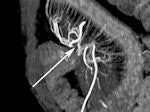

Increased mesenteric vascularity.

The problem was solved when researchers inadvertently tried a negative oral contrast medium.

"It became apparent that just filling the small bowel with negative contrast, food, or fluid was actually better than very bright contrast," Higgins said.

Decades of experience with barium imaging taught radiologists the value of complete bowel dissention for ensuring thorough examination. The use of neutral enteric contrast agents has proved to be especially well-suited for this role. Such agents allow water in the gut to remain there without bowel wall absorption, Higgins said.